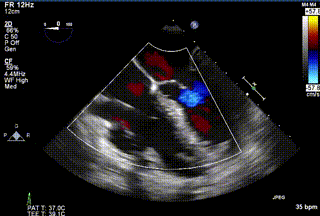

2021年12月24日,復旦大學附屬中山醫院葛均波院士團隊成功應用LuX-Valve Plus為一例極重度三尖瓣反流(TR)合并房顫、房缺的患者完成了經血管三尖瓣置換術,這是在前基礎上,本周完成的第三例經血管三尖瓣置換手術,葛均波院士、周達新教授等與心外科魏來教授、賴顥教授,心超室的潘翠珍教授、李偉教授及麻醉科的郭克芳教授共同完成了本周手術,均獲得圓滿成功!患者術后超聲顯示無TR,臨床癥狀明顯改善。本周手術的成功也為LuX-Valve Plus救治性臨床研究添上了濃墨重彩的一筆。

三例患者入院后,葛均波院士團隊周達新教授、潘文志教授、張源博士、陳莎莎博士及心超室的潘翠珍教授、李偉教授對患者的情況進行詳細評估和討論,最終決定為三例患者選擇LuX-Valve Plus40mm、50mm和50mm型號的瓣膜進行手術治療。手術后即刻拔除氣管插管,術后患者三尖瓣反流癥狀得到顯著改善,復查心超結果顯示人工三尖瓣瓣膜支架固定穩定,瓣葉關閉形態未見異常,未見明顯反流。